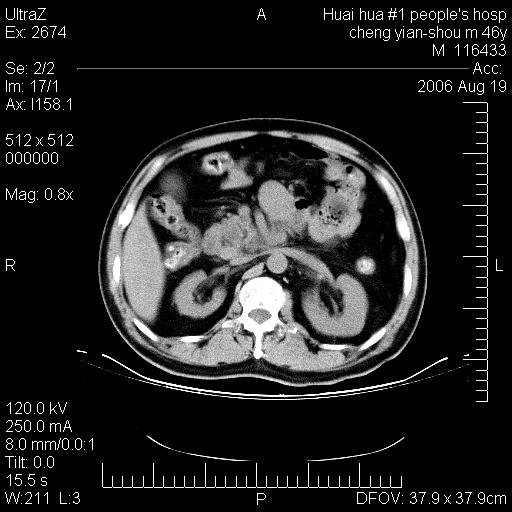

患者,男,46y。腹痛2月,消瘦。

十二指肠水平段占位,考虑间质瘤或平滑肌瘤。

肿块较大,腹膜后占位,境界欠清,周边脂肪密度较高呈条状影,有没有脂肪肉瘤可能,

缺少完整的三期图像。考虑肠系膜脂膜炎mp(肿块型)。

鉴别:间质瘤(这么大而无囊变不可思议)、平滑肌瘤/肉瘤、淋巴瘤、类癌,脂肪类肿瘤、转移瘤等。

十二指肠水平段占位,考虑间质瘤。

首先考虑小肠间质瘤。

十二指肠水平段软组织密度占位,考虑间质瘤可能性大。

腹膜后占位,境界欠清,考虑来源于十二指肠病变,间质瘤或平滑肌肉瘤可能性大。建议活检。

手术病理结果:原发性小肠恶性淋巴瘤(primary gastrointestinal lymphoma,pgil)是原发于胃肠的淋巴网织系统的恶性肿瘤,在结外淋巴瘤中居第一位,该病少见,临床无特异性,诊断困难,术前主要依靠影像学诊断。胃肠道本身具有较丰富的淋巴组织,因而胃肠原发性淋巴瘤是结外淋巴瘤最常见的部位,文献报道约占胃肠道恶性肿瘤的1%~4%,其中胃约占50%~70%,小肠约占35%~70%,结肠约占4%~6%。影像检查在pgil的诊断及分期中有重要的作用,ct是很有价值的检查方法。

胃肠淋巴瘤病理特点:胃肠道原发性淋巴瘤起源于胃肠壁固有层和黏膜下层的淋巴组织即胃肠粘膜相关淋巴组织(malt),多为粘膜相关淋巴瘤。病理上通常为非霍奇金淋巴瘤,且决大多数来源于b淋巴细胞,很少见于霍奇金淋巴瘤。胃肠原发淋巴瘤比胃肠道癌的发病率要低的多,最常见于胃,其病因可能跟幽门螺杆菌感染有关。幽门螺杆菌能引起胃粘膜损害,引起炎性及免疫反应,淋巴细胞聚集并形成滤泡,可影响胃的正常生理功能,导致胃淋巴瘤的发生。单纯性小肠淋巴瘤是常见好发于回盲末端,受累的肠段较长,可单发、多发,甚至累及整个小肠。原发性大肠淋巴瘤罕见,以直肠和盲肠最多见。病变大体观可表现为胃肠腔内外的肿块,也可表现为从黏膜下到浆膜面肠壁的纵向浸润,并且常常伴有肠系膜淋巴结肿大。任何情况下,肿瘤几乎总是导致一定程度的肠壁增厚,可对称或不对称,病变与正常组织间常无明确分界,肠腔可狭窄、正常或动脉瘤样扩张,后者主要是肿瘤在肠壁内浸润,破坏肠壁内植物神经丛所致。以上改变成为ct检测病变的病理基础。

肠道淋巴瘤的ct表现分为4类

1) 壁内浸润型, (2)多发结节型, (3)肠系膜受累伴腔外肿块型(本型就是),(4)肿块型。